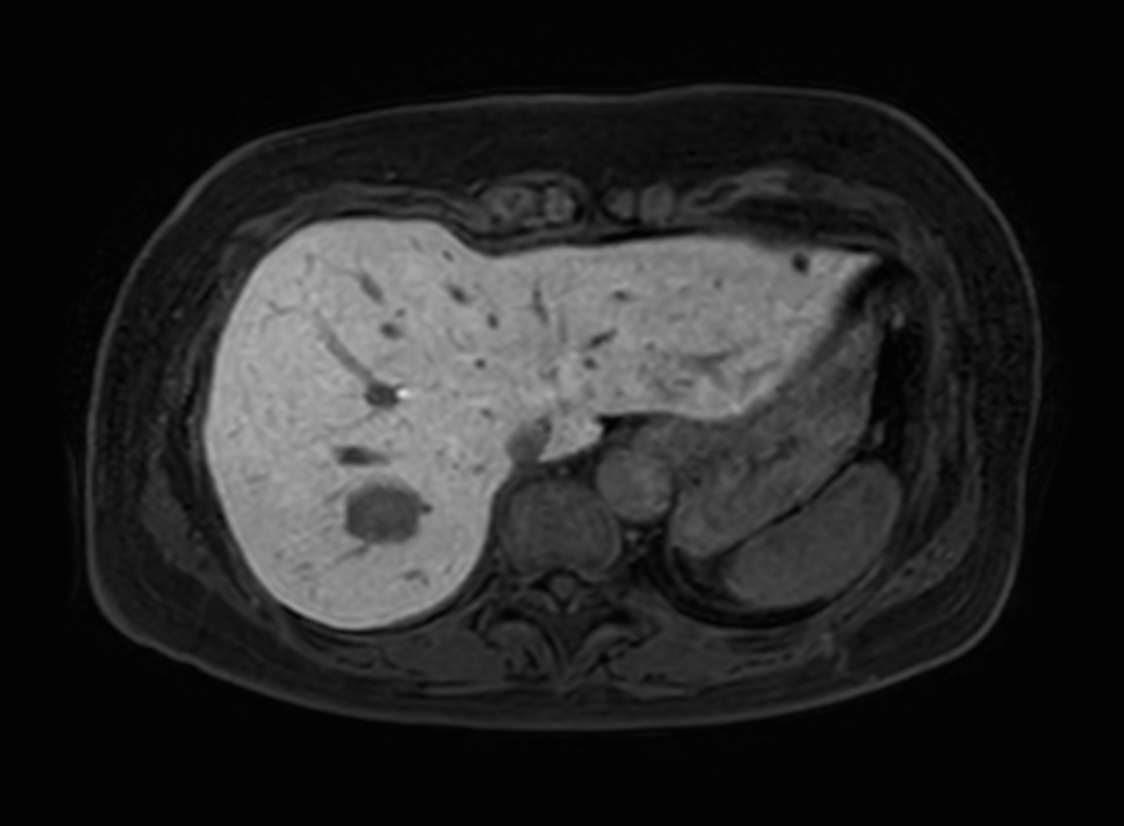

Axial eTHRIVE (1st dynamic)